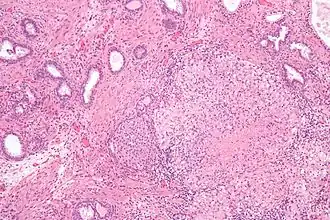

![]() Гранулёматозный простатит вследствие лечения рака мочевого пузыря вакциной БЦЖ | |

Гистопатологические находки при гранулёматозном простатите

При гистологическом исследовании биоптата ткани предстательной железы больного гранулёматозным простатитом обнаруживается значительная деструкция ацинарных протоков предстательной железы, инфильтрация предстательной железы эпителиоидными клетками, гигантскими клетками, лимфоцитами, плазматическими клетками и гистиоцитами, а также плотный фиброз (разрастание соединительной ткани и замещение ткани предстательной железы соединительной тканью).